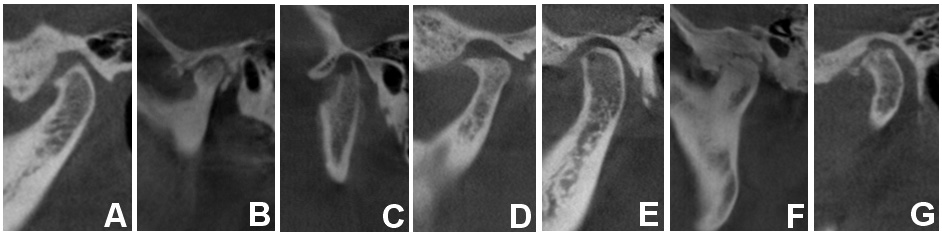

Previously reported definitions of flattening (Figure 2A), sclerosis (Figure 2B), erosion (Figure 2C), osteophytes (Figure 2D), subchondral cyst (Ely’s cyst) (Figure 2E), ankylosis (Figure 2F), and loose joint bodies (Figure 2G), evaluated degenerative changes of the condylar head.17, 18

The TMJs were classified into 2 groups: (1) without-change (when the condyles had a smooth, clear cortical bone surface); and (2) with-change (flattening, erosion, osteophytes, sclerosis, subchondral cyst, ankylosis, and/or loose joint bodies).